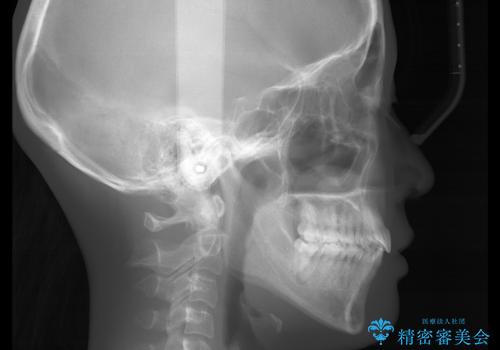

- 以前からコンプレックスだった八重歯の治療を主訴にご来院されました。

検査の結果、抜歯をすることでスペースを作って並べる方法が選択され、ワイヤー装置を用いた治療を開始することとなりました。

奥歯の上下のズレ等は軽度で、必要なスペースと抜歯により作られるスペースがほぼ等量だったため治療の単純化が計れ、大きな移動・見た目の劇的な変化に対して比較的早期での治療完了となりました。

叢生の度合いが重く、抜歯が必要なケース。八重歯の部分以外には大きな問題は認められなかったため、劇的変化が起こる治療でも比較的短期間で終了することができました。